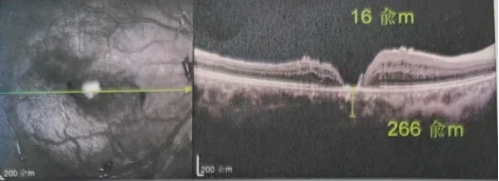

最讓吳爺爺難以置信的是:術(shù)后只需保持平躺24小時(shí)!第二天復(fù)查時(shí),眼底鏡及OCT檢查清晰顯示——那個(gè)折磨了他大半年的大裂孔,竟然閉合了!且吳爺爺?shù)挠已垡暳τ辛嗣黠@的改善,術(shù)后3天已經(jīng)可以看到 0.15。

李海波博士后表示:如果來(lái)得更早一些,他的視力還可以恢復(fù)得更好。但現(xiàn)在的治療結(jié)果對(duì)于經(jīng)歷過兩次失敗手術(shù)和漫長(zhǎng)煎熬的他而言,已是奇跡。